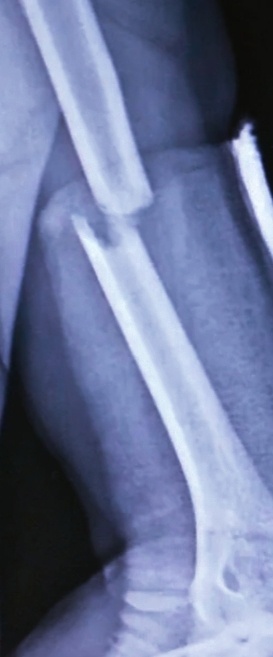

Завел травматолог пациентку:

–Можно , гляну , как спицы пошли , если не пошли в стационар ее заберу.

Сняла, проявила:

-Ну как? Вроде же попали?

-Вроде да, ну , а боковой еще глянем , убедиться хочу.

Сделали боковой:идеально!

-Фух , полчаса возился , думал , а вдруг нет , опять несвежий перелом!

-Знаете , мастерство -оно такое!

Отправила снимок.